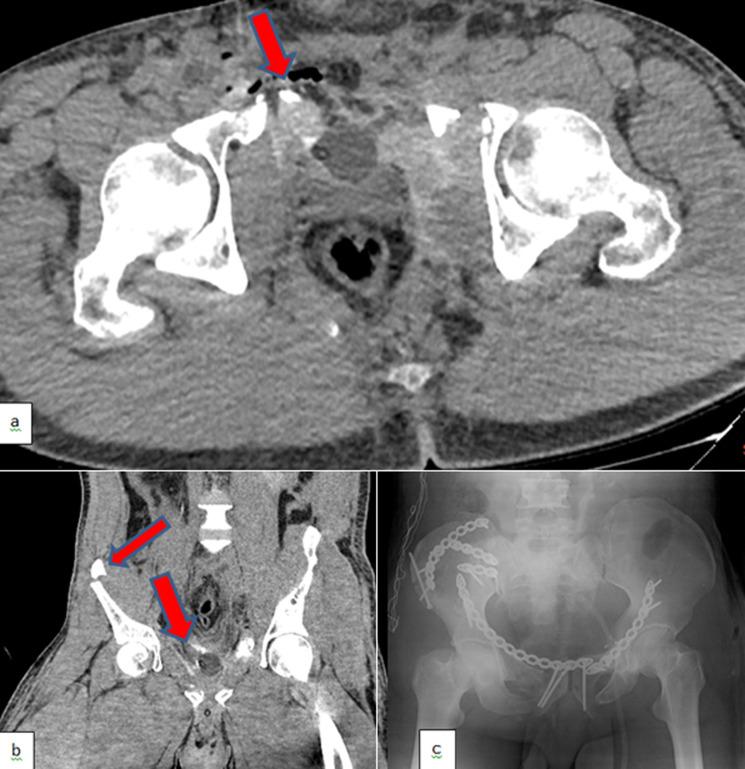

It is evident that Acute Kidney Injury (AKI) is an independent risk factor for both the survival of patients and their kidneys. Here, we present a case of oliguric AKI secondary to blunt trauma-induced crush syndrome complicated with severe sepsis in which the patient had a complete recovery of kidney functions after 3 months of dialysis dependency. A 40-year-old male construction worker had a severe episode of work accident. He had fallen into the stream from a height of 6 meters and the concrete pillars of the bridge fell over him. He had an iliac artery injury, crush-related acute kidney failure, a ruptured bladder, multiple fractures in the lumbar vertebral spinous and transverse processes, bilateral pelvic rami, acetabulum, and bilateral iliac wings. Despite 3 months of dialysis dependency with multiple episodes of sepsis and nephrotoxic antibiotic applications, fortunately, recovery of kidney functions (creatinine clearance >20 mL/min) was achieved. The creatinine clearance of the patient was calculated as 78 mL/min one year after discharge from the hospital. It is well-known that severe trauma leading to severe sepsis and severe AKI has catastrophic effects on the survival of patients. In addition, nephrotoxic antibiotics and contrast media had to be given to our patient, which resulted in further injury. A multidisciplinary (including nursery care) approach, early and proper treatment of sepsis, pulmonary rehabilitation, enteral/parenteral nutritional support, and appropriate timing, prescription, and dose of dialysis are fundamental factors playing a major role in the recovery of prolonged AKI as in our patient.